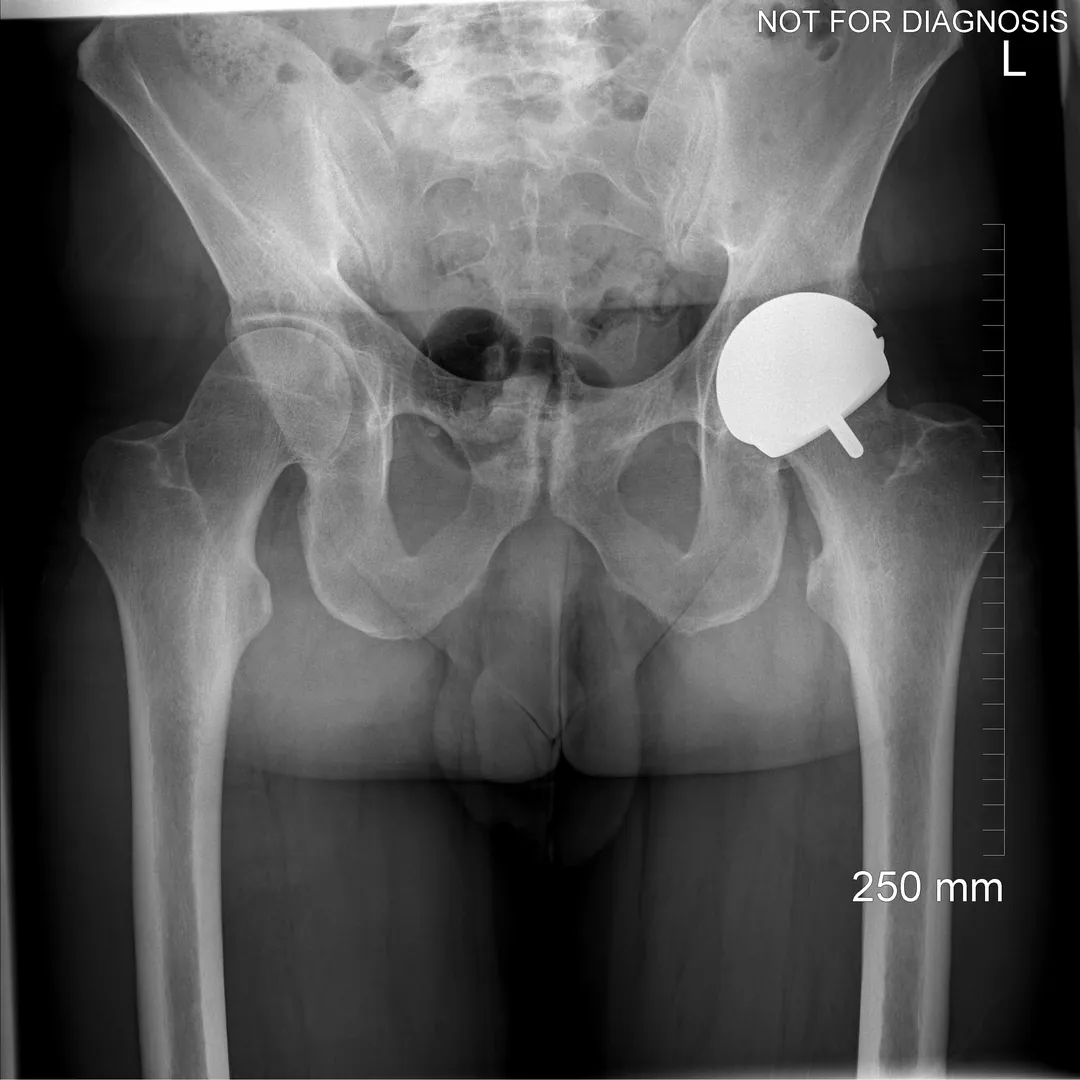

Hip resurfacing is a type of hip surgery used to treat hip arthritis, most commonly in younger and more active patients. Unlike a total hip replacement, hip resurfacing preserves more of your natural thigh bone. Instead of removing the entire femoral head (ball at the top of the thigh bone), the damaged surface is trimmed and covered with a smooth metal cap. The hip’s socket on the pelvis is also fitted with a metal cup.

Dr Grammatopoulos will review your X-rays and other imaging carefully to determine whether hip resurfacing is an appropriate option for you.

Hip Resurfacing

- Preserves more natural bone (the femoral head is capped rather than replaced)

- Uses a larger ball size, which may reduce the risk of dislocation